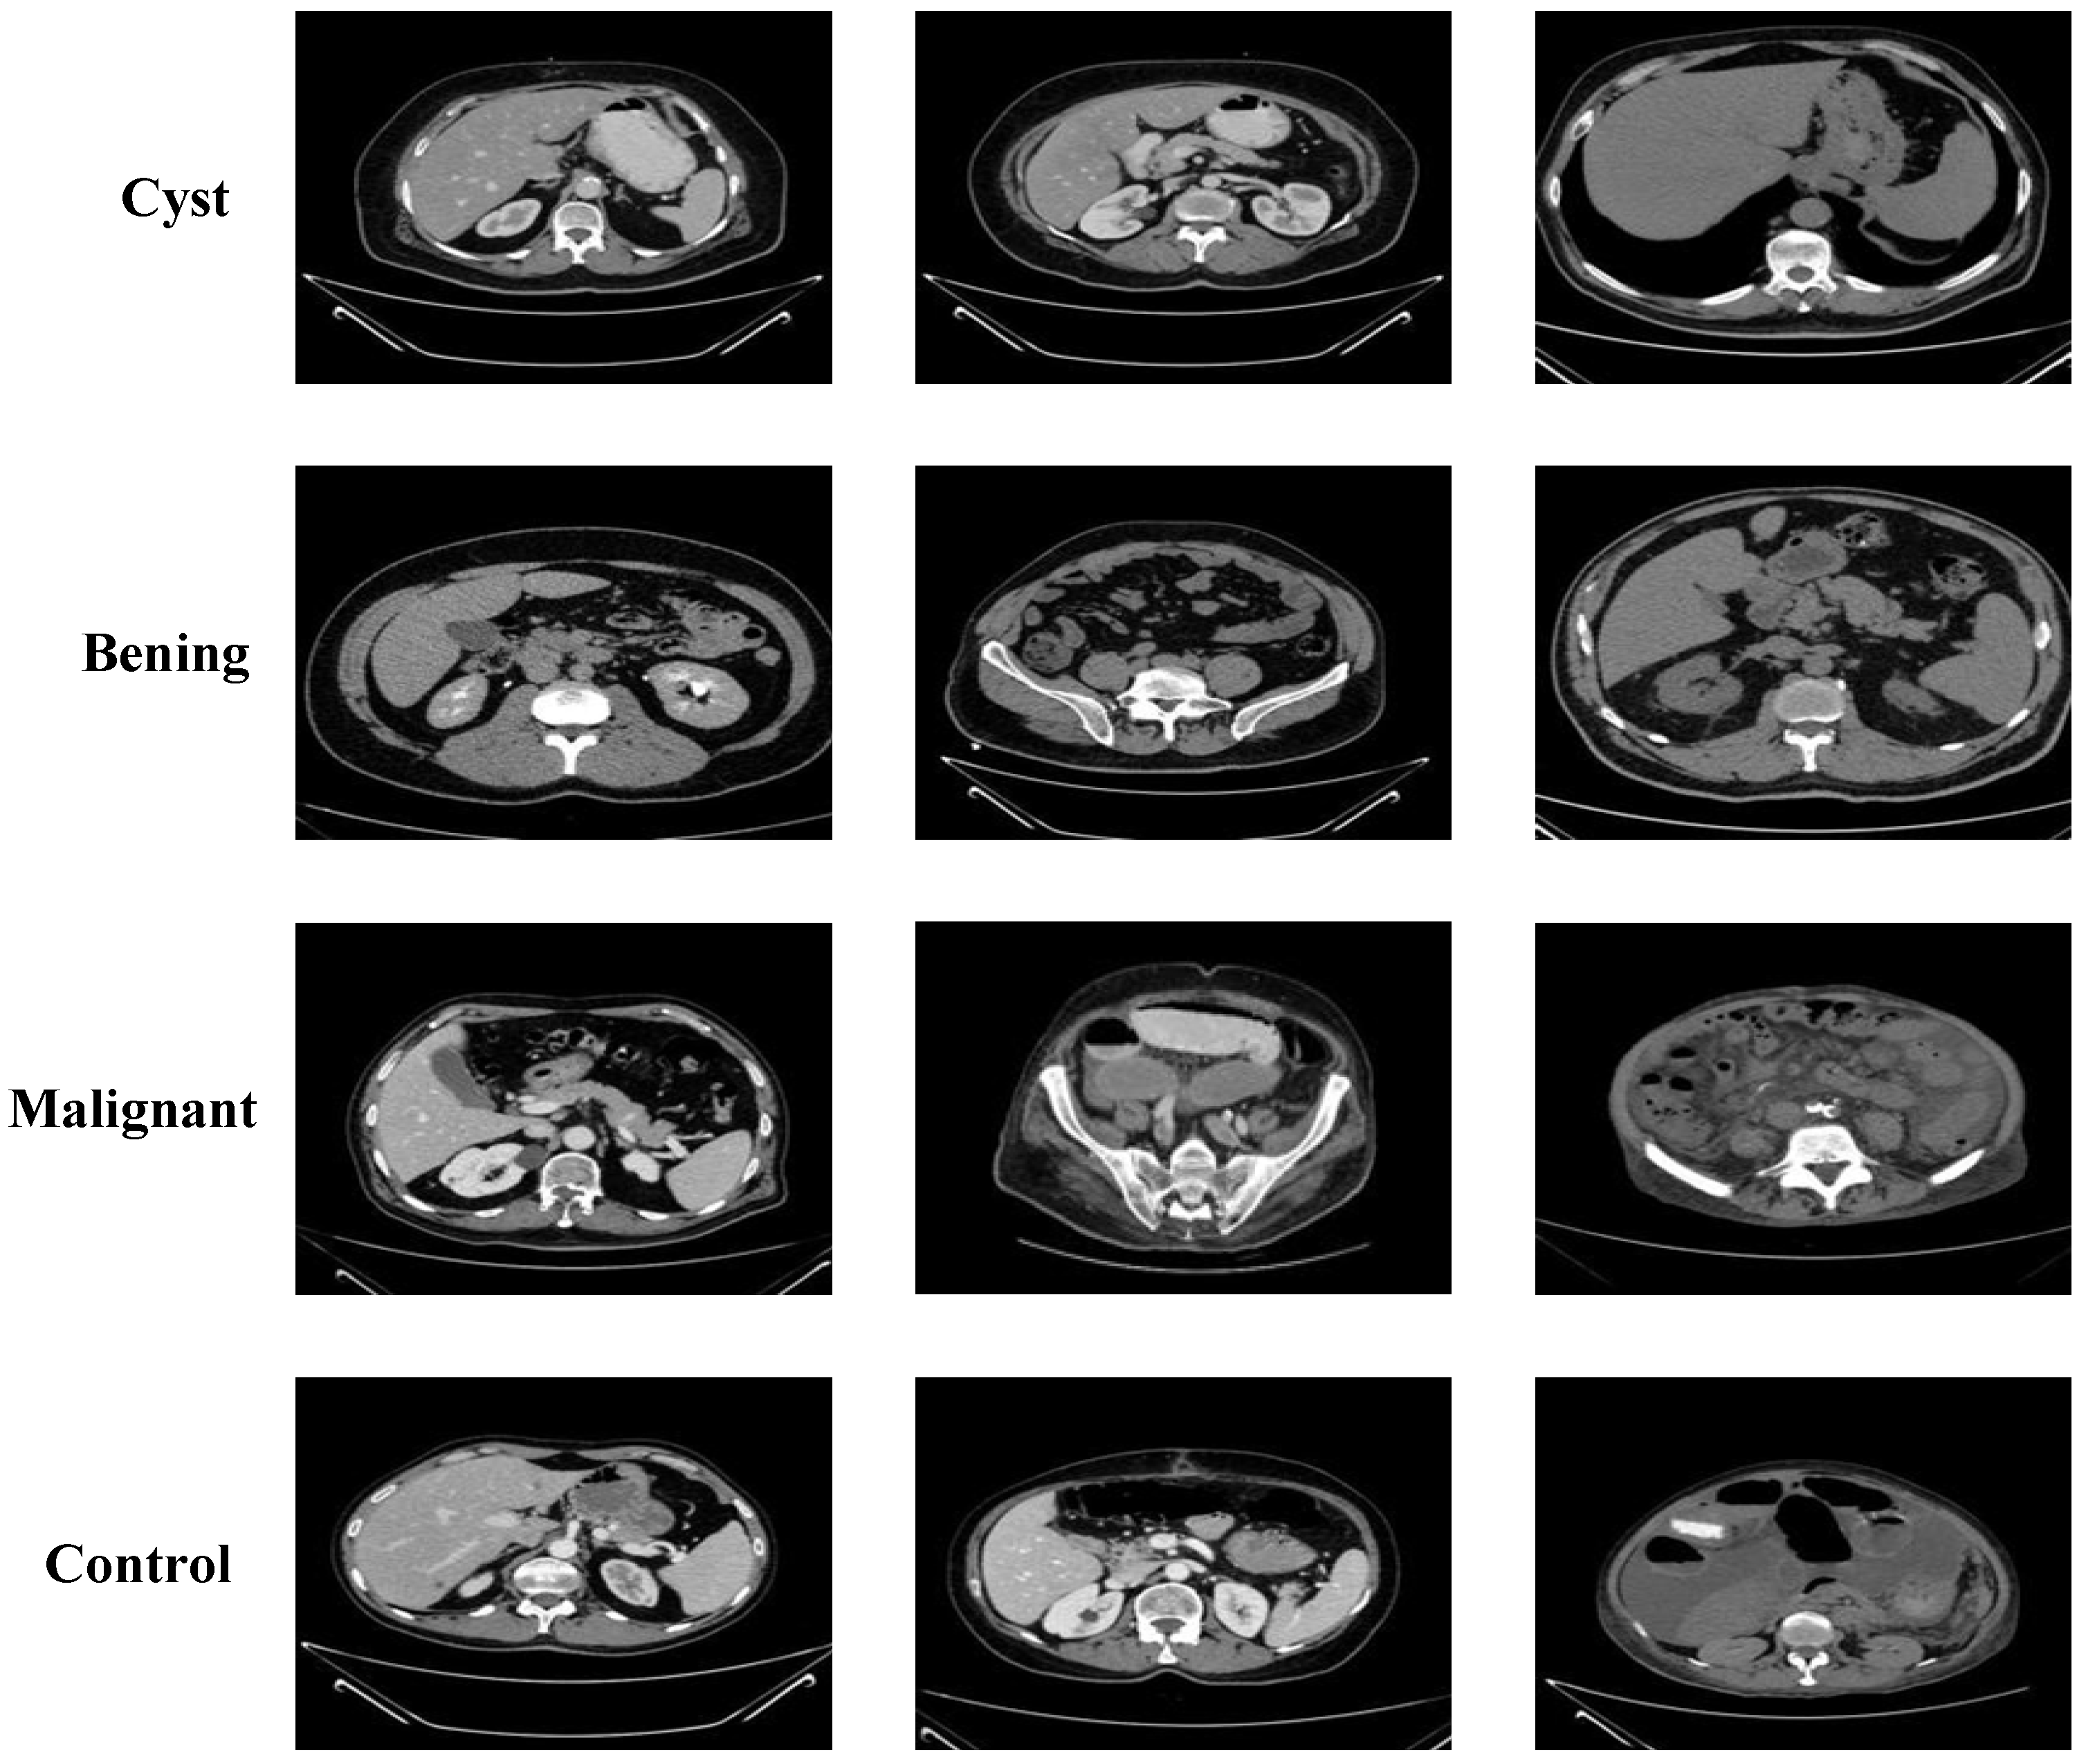

3.2. Performance Evaluation on Kaggle CT KIDNEY Dataset

3.3. Performance Evaluation on KAUH: Jordan Dataset

| Class | Train Image Count | Test Image Count |

|---|---|---|

| Cyst | 3557 | 1332 |

| Normal | 4875 | 1828 |

| Stone | 1329 | 502 |

| Tumor | 2187 | 818 |

| Benign | 2128 | 532 |

| Cyst | 1064 | 266 |

| Malignant | 1232 | 308 |

| Normal | 1792 | 448 |